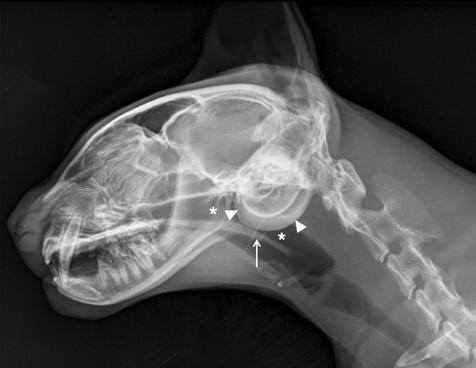

1. Radiografías de la cabeza de un gato maine coon de un año de edad. (A) Proyección lateral. (B) Proyección dorsoventral. (C) Rostro 10º ventrodorsocaudal oblicua.

Se presentó en consulta un gato macho castrado de raza maine coon, de un año de edad y 5,8 kg de peso, remitido con historia de otitis externa desde hacía un mes.

En la exploración otológica se visualizó una masa en el conducto auditivo externo izquierdo, apreciable desde la abertura del pabellón auricular. La masa era sólida, poco móvil y obstruía totalmente el canal auditivo. El resto del examen físico y pruebas de enfermedades víricas fueron normales. En el análisis sanguíneo se evidenció neutrofilia con desviación a la izquierda y trombocitosis.